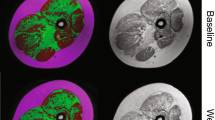

To prepare qMRI end-points for clinical trials, it is important to know in which muscle groups fatty replacement will progress in the absence of remedial treatment, as rates of progression vary between different muscle groups and over time. The most suitable muscle group to follow will depend on several factors, including age, type of disease, and mechanism of action of the drug. For instance, the efficacy of a drug that is thought to prevent a further increase in fat replacement would be most suitable to test in a muscle and age group where there is a clear increase in fat replacement over time. This muscle group will then have the highest standardized response mean. In DMD, for instance, it has been suggested that between the ages of 9 and 11 years, the vastus lateralis has the highest standardized response mean [10]. On the other hand, a drug that aims to increase muscle mass can also be evaluated in a muscle that does not show fat replacement yet, merely by assessing at the contractile volume. Table 3 outlines the longitudinal studies that have been performed in different muscular dystrophies to measure the rates of progression. Figure 6 shows two examples of fat fraction progression across 1 year in a slow-progressing muscular dystrophy, LGMD2I [11], and one in the more rapidly progressing DMD. Most of these studies have examined the natural history of different diseases, though Arpan et al. 2014 considered the effects of corticosteroid initiation in DMD boys [35] and Carlier et al. 2015 [42] examined the effect of enzyme replacement therapy in late-onset Pompe’s disease. Commonly, these longitudinal studies contrast the increase in muscle fat fraction revealed by qMRI and disease progression demonstrated by the standard physical function tests that are routinely used in clinical care and clinical trials. These studies have demonstrated the enhanced sensitivity of qMRI compared to the existing measurements in both the legs [9,10,11, 24, 43] and the arms [8, 44].

Example of using PDFF maps to assess progression at baseline (left) and 12 months later (right) in the lower leg of a patient with limb girdle muscular dystrophy 2I (bottom) and Duchenne muscular dystrophy (top). Progression in 1 year is generally much more rapid in DMD compared to LGMD2I: fat fraction changes measured included the soleus (21–28% in DMD, 8–13% in LGMD2I), tibialis anterior (12–16% in DMD, no change at 6% in LGMD2I), lateral gastrocnemius (21–29% in DMD, 20–24% in LGMD2I), medial gastrocnemius (15–20% in DMD, 29–49% in LGMD2I), and the peroneus (28–36% in DMD, 18–26% in LGMD2I)